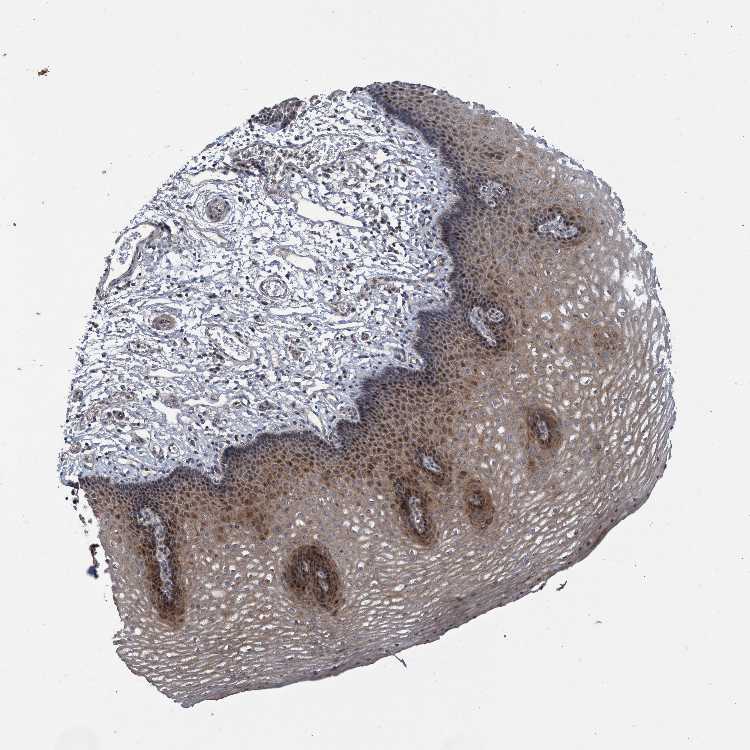

ESOPHAGUS - Antibody stainingi

Antibody staining in the annotated cell types in the current human tissue is reported as not detected, low, medium, or high, based on conventional immunohistochemistry profiling in selected tissues. This score is based on the combination of the staining intensity and fraction of stained cells.

Each image is clickable and will lead to virtual microscopy that enables deeper exploration of all samples and also displays staining intensity scores, fraction scores and subcellular localization as well as patient and tissue information for each sample.

Antibody HPA023106

Squamous epithelial cells Medium